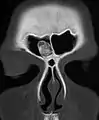

| Osteoma of external auditory meatus | |